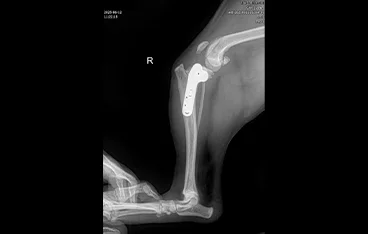

• PLATE

• PLATE 수술 전

PLATE 수술 후